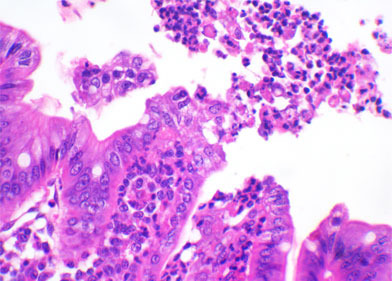

L’évaluation histologique des fragments intestinaux cités dans l’article précédent devrait permettre la suspicion de l’agent possiblement impliqué dans le processus et dans certains cas, définir la présence d’agents infectieux. Par exemple, l’atrophie des villosités peut être due par les coccidies (I. Suis), les Rotavirus, le GETv, le PEDv, le Deltacoronavirus ou aussi C. perfringens de type A. Si les échantillons appartiennent à des porcelets de plus de 5 ou 6 jours, on peut trouver des formes sexuées ou asexuées d’I. suis dans le cytoplasme des entérocytes de l’extrémité des villosités. Si on ne trouve pas de coccidies, on peut réaliser une immunohistochimie pour détecter la présence d’antigènes viraux de Rotavirus ou de Coronavirus dans les entérocytes. Dans presque tous les cas d’ETEC, l’examen histologique permettra la détection d’une myriade d’organismes cocobacillaires adhérents à la superficie de l’entérocyte sur la base ou sur la paroi latérale des villosités. C. perfringens de type C entrainerait une lésion transmurale fibrinonécrotique et hémorragique de répartition segmentaire dans l’intestin grêle. C. difficile est le seul agent infectieux qui causera des lésions dans le gros intestin. On observe souvent l’œdème du mésocôlon. Les principales découvertes dans les cas d’infection par C. difficile sont la diminution des cellules caliciformes et une grande infiltration de neutrophiles dans la muqueuse du côlon qui dans certains cas, rompent l’épithélium comme une éruption volcanique. C. perfringens de type A est le plus difficile à déterminer par histopathologie puisqu’il peut entraîner une atrophie des villosités mais le fait de ne pas trouver cette lésion n’écarte pas cette possibilité.